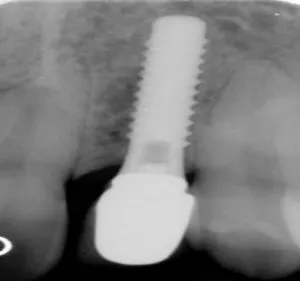

Antes: paciente con dos dientes frontales ausentes con pérdida de hueso y encía. 7 años después de colocación de implantes con injerto de hueso y encía